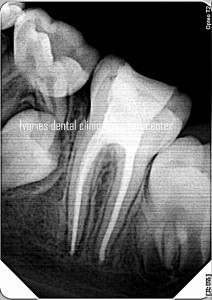

- Role of a pre-operative radiograph

- CASE DISCUSSION & ESTABLISHING DIAGNOSIS WITH RADIOGRAPHS